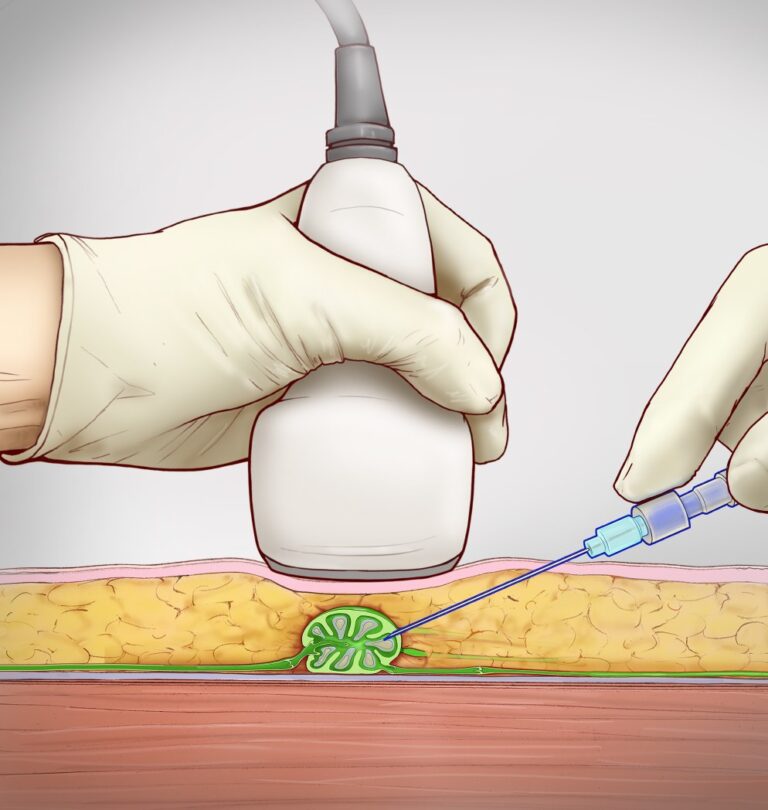

In this technique, an inguinal lymph node is directly accessed under ultrasound guidance with a 25-gauge spinal needle with the needle tip positioned in the hilum of the node (Figure 1). Subsequently, an oil-based contrast agent (Lipiodol, Guerbet Group, Princeton, NJ) is injected at a rate of about 1-2 mL per 5 minutes (Figure 2). If successful, immediate opacification of the lymphatic vessels is observed under fluoroscopy (Figure 3).